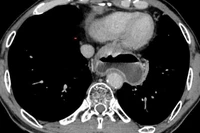

Qua khám và siêu âm nội soi, các bác sĩ khoa Nội soi-Thăm dò chức năng xác định bệnh nhân có khối u cơ trơn thực quản lớn, kích thước 16×50mm, chiếm tới 4/5 chu vi lòng thực quản lan rộng xuống vùng thân vị dạ dày, một trong các vị trí khó và phức tạp nhất của can thiệp nội soi.